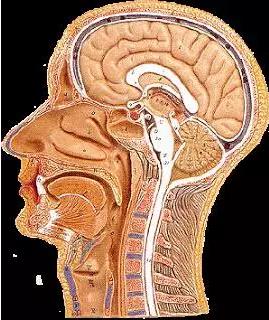

我們從外往里看吧。生物學有時似乎非常讓人滿意,比如你的頭上有一個真正的俄羅斯套娃。

你有頭發,然后是頭皮,你認為下面就是你的頭骨了——但實際上頭骨之上還有19樣東西。

你的頭骨下面,又是一大堆東西,之后才是你的大腦:

在你的頭骨下面,大腦周圍有三個膜,將大腦環繞:

在外面,有硬腦膜,堅固耐用,防水。硬腦膜與顱骨齊平。我聽到有人說,大腦中沒有疼痛感覺區,但硬腦膜實際上能感覺疼痛,且和你的面部肌膚一樣敏感,硬膜上的壓力或挫傷往往造成了人們嚴重的頭痛。

然后下面是蛛網膜,這是一層皮膚,然后是帶有彈性的纖維的開放空間。我一直以為我的大腦只是漫無目的地漂在我大腦中的某種液體里,但實際上,腦外和顱骨內壁之間的唯一真正的空間差距是這個蛛網膜。這些纖維穩定了大腦的位置,因此不能動作太大,他們充當減震器,當你的頭撞到東西。這個區域充滿了脊髓液。

最后,是軟腦膜,和腦外融合的很精巧的皮膚層。你知道,當你看到一個大腦,它總是覆蓋著惡心的血管。但這些并不是真正在大腦的表面上,它們埋設在里面。

下面是完整的樣子,使用的樣品可能是豬的大腦:

從左到右是皮膚(粉紅色),然后是兩個頭皮層,然后是頭骨,然后是硬腦膜,蛛網膜,最右邊是只由軟腦膜覆蓋的大腦。

我們從外往里看吧。生物學有時似乎非常讓人滿意,比如你的頭上有一個真正的俄羅斯套娃。

你有頭發,然后是頭皮,你認為下面就是你的頭骨了——但實際上頭骨之上還有19樣東西。

你的頭骨下面,又是一大堆東西,之后才是你的大腦:

在你的頭骨下面,大腦周圍有三個膜,將大腦環繞:

在外面,有硬腦膜,堅固耐用,防水。硬腦膜與顱骨齊平。我聽到有人說,大腦中沒有疼痛感覺區,但硬腦膜實際上能感覺疼痛,且和你的面部肌膚一樣敏感,硬膜上的壓力或挫傷往往造成了人們嚴重的頭痛。

然后下面是蛛網膜,這是一層皮膚,然后是帶有彈性的纖維的開放空間。我一直以為我的大腦只是漫無目的地漂在我大腦中的某種液體里,但實際上,腦外和顱骨內壁之間的唯一真正的空間差距是這個蛛網膜。這些纖維穩定了大腦的位置,因此不能動作太大,他們充當減震器,當你的頭撞到東西。這個區域充滿了脊髓液。

最后,是軟腦膜,和腦外融合的很精巧的皮膚層。你知道,當你看到一個大腦,它總是覆蓋著惡心的血管。但這些并不是真正在大腦的表面上,它們埋設在里面。

下面是完整的樣子,使用的樣品可能是豬的大腦:

從左到右是皮膚(粉紅色),然后是兩個頭皮層,然后是頭骨,然后是硬腦膜,蛛網膜,最右邊是只由軟腦膜覆蓋的大腦。